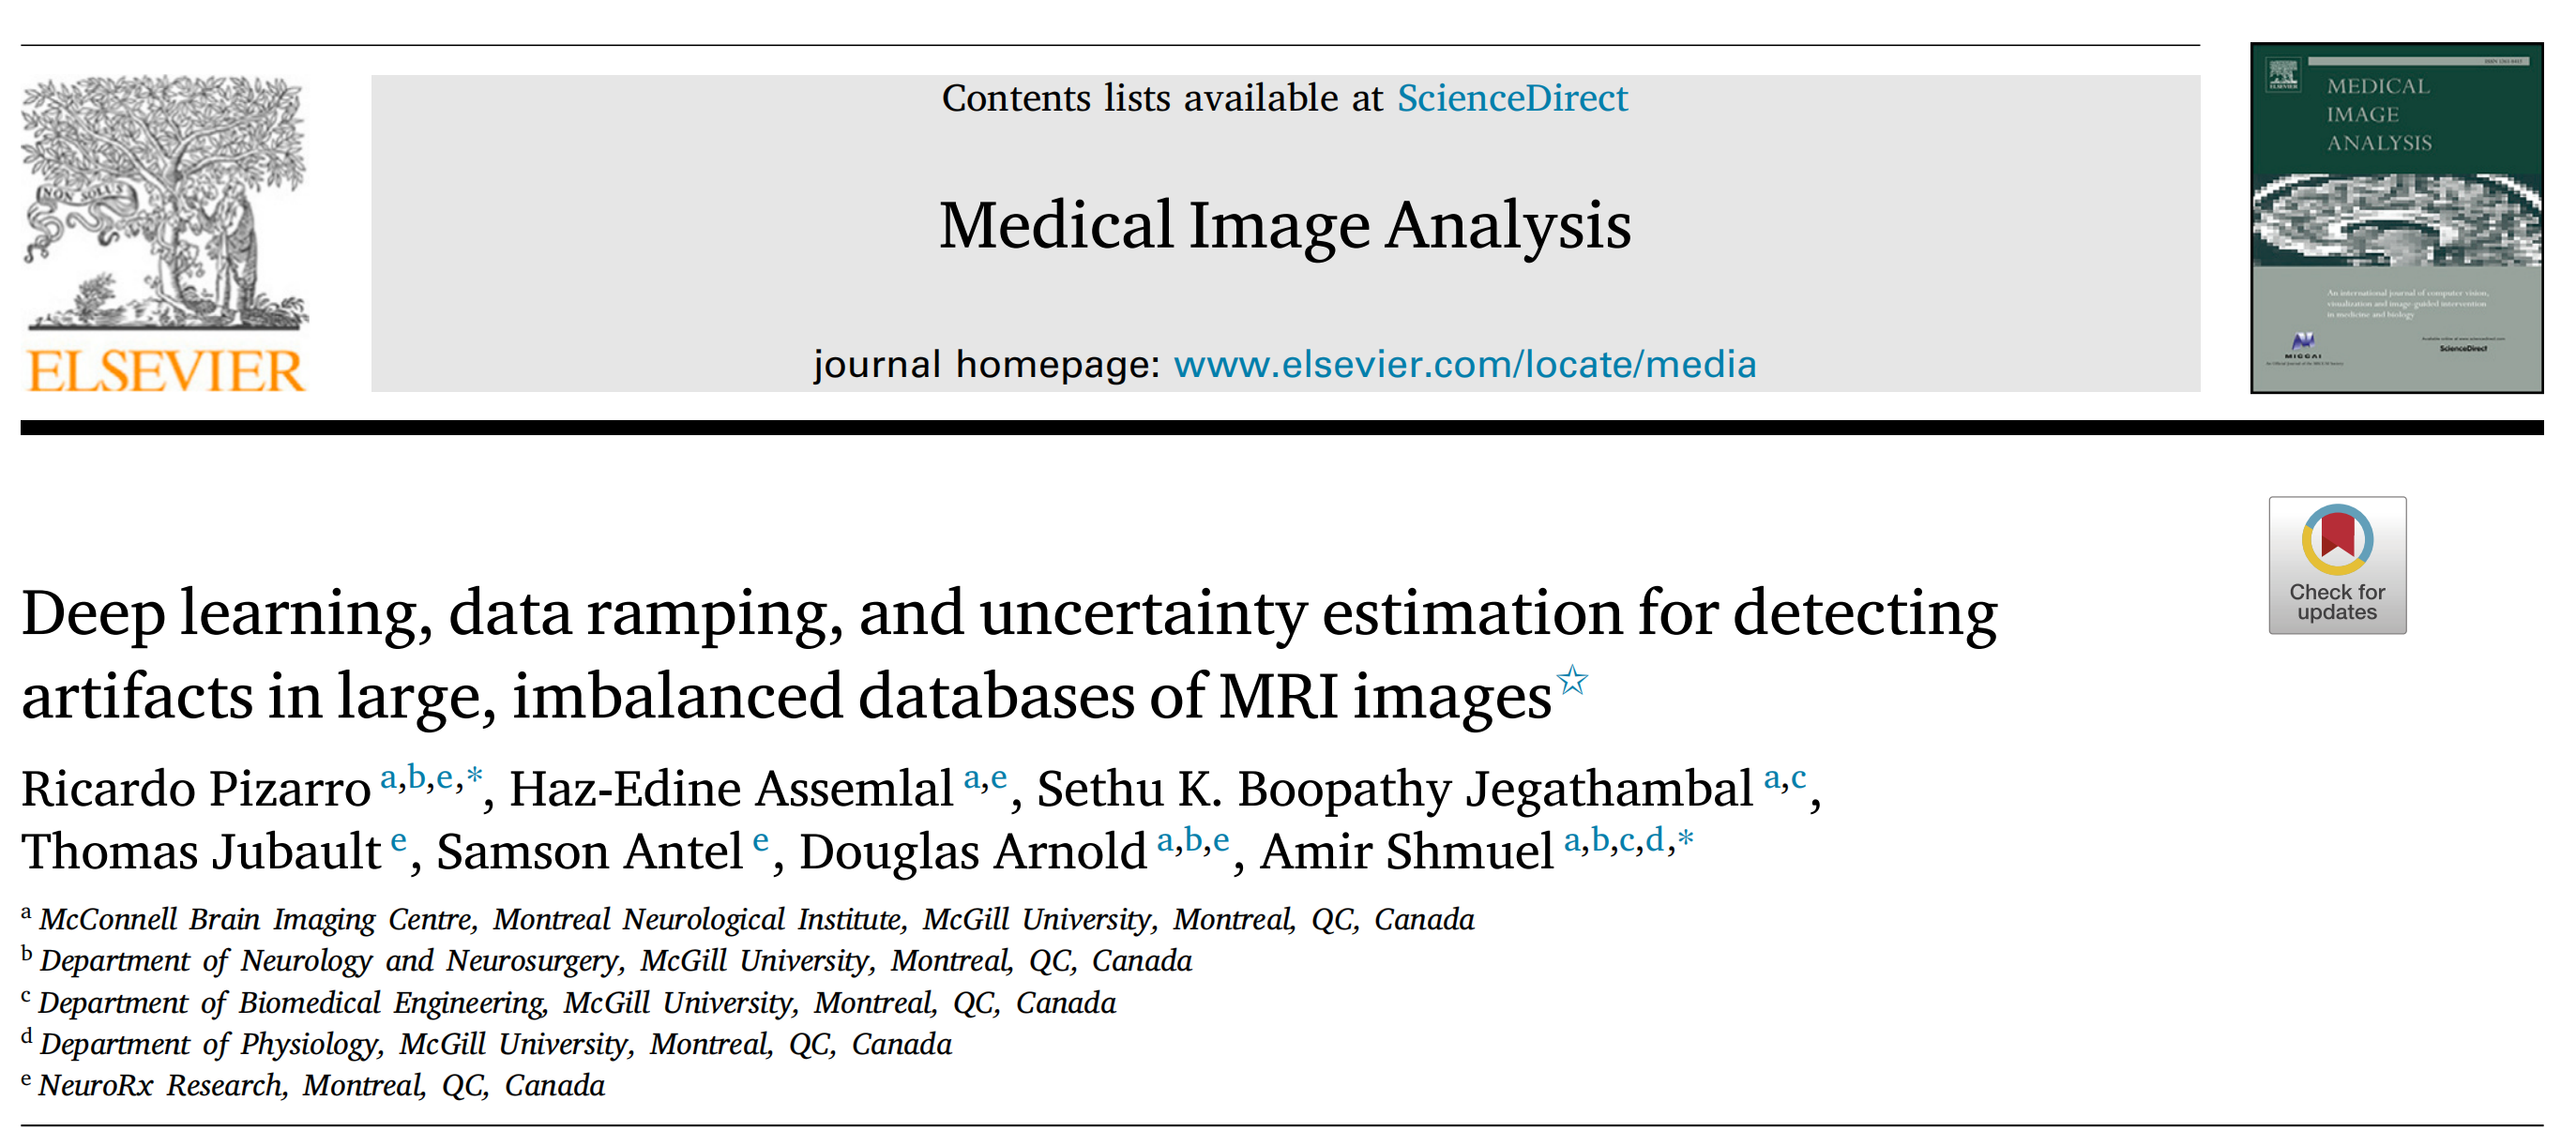

Fig. 1展示了数据库中最常见的三种伪影实例。

下面是对这三种伪影的分析:

覆盖伪影(Coverage Artifact):

- 原因:由于视场(Field of View, FOV)放置不当导致。

- 表现:通常会导致包裹效应(wrap around),即图像的一侧信息错误地显示在另一侧,这可能会误导对图像的解读。

- 影响:覆盖伪影可能会影响图像分析的准确性,尤其是在进行形态学研究时,错误的图像覆盖会导致对脑组织体积或形状的错误测量。

强度伪影(Intensity Artifact):

- 原因:由金属植入物引起的磁敏感性问题。

- 表现:在金属植入物附近产生异常的信号强度,这可能会导致图像的某些区域出现过度亮或暗的区域。

- 影响:强度伪影可能会干扰对脑部病变的检测和分析,因为它们可能会被误认为是病理变化,或者掩盖真实的病变。

运动伪影(Motion Artifact):

- 原因:由于头部运动引起。

- 表现:包括吉布斯环(Gibbs ringing),这是一种在快速变化的信号(如头部运动产生的信号)附近出现的振荡或“振铃”效应。

- 影响:运动伪影可能会导致图像模糊,影响对脑部结构细节的观察,进而影响诊断的准确性。

这些伪影的存在强调了在进行MRI图像分析之前,进行质量控制和伪影检测的重要性。自动化的伪影检测方法,如本文提出的深度学习方法,可以帮助提高MRI图像分析的效率和准确性,从而为临床研究和诊断提供更可靠的数据。